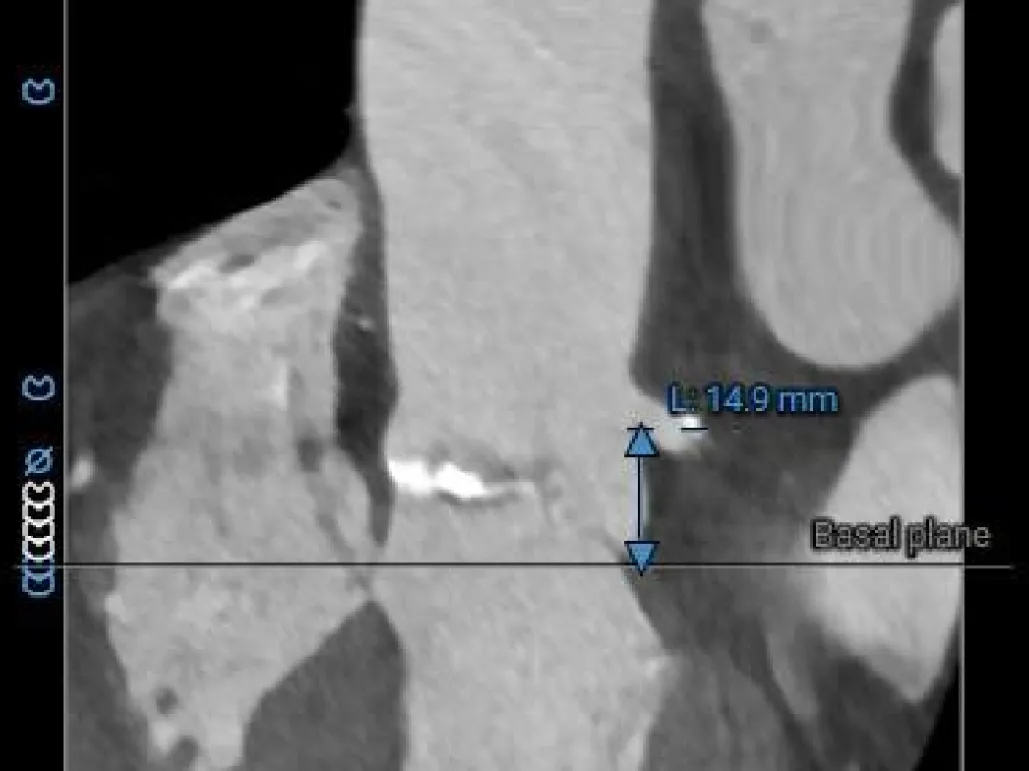

冠脉风险评估

LCA Height

RCA Height